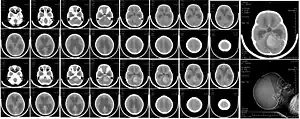

_in_adult.JPG.webp)

Histologicamente, o tumor é sólido, rosa cinzento e bem circunscrito. O tumor é muito celular, com muitas mitoses, pouco citoplasma e tem a tendência de formar aglomerados e rosetas.